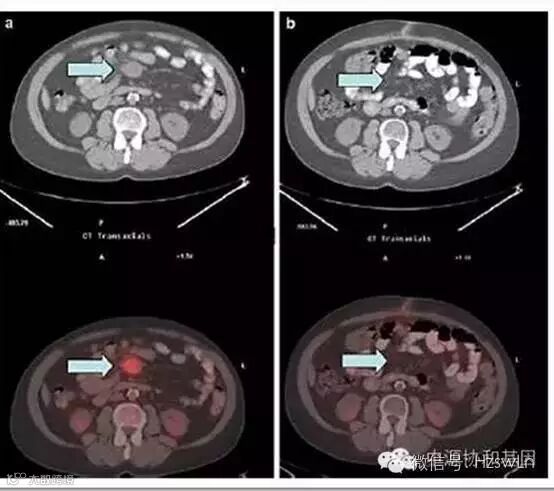

克唑替尼用药三个月后PET-CT扫描表明腹部肿块完全消失。

克唑替尼治疗前 克唑替尼治疗3个月后